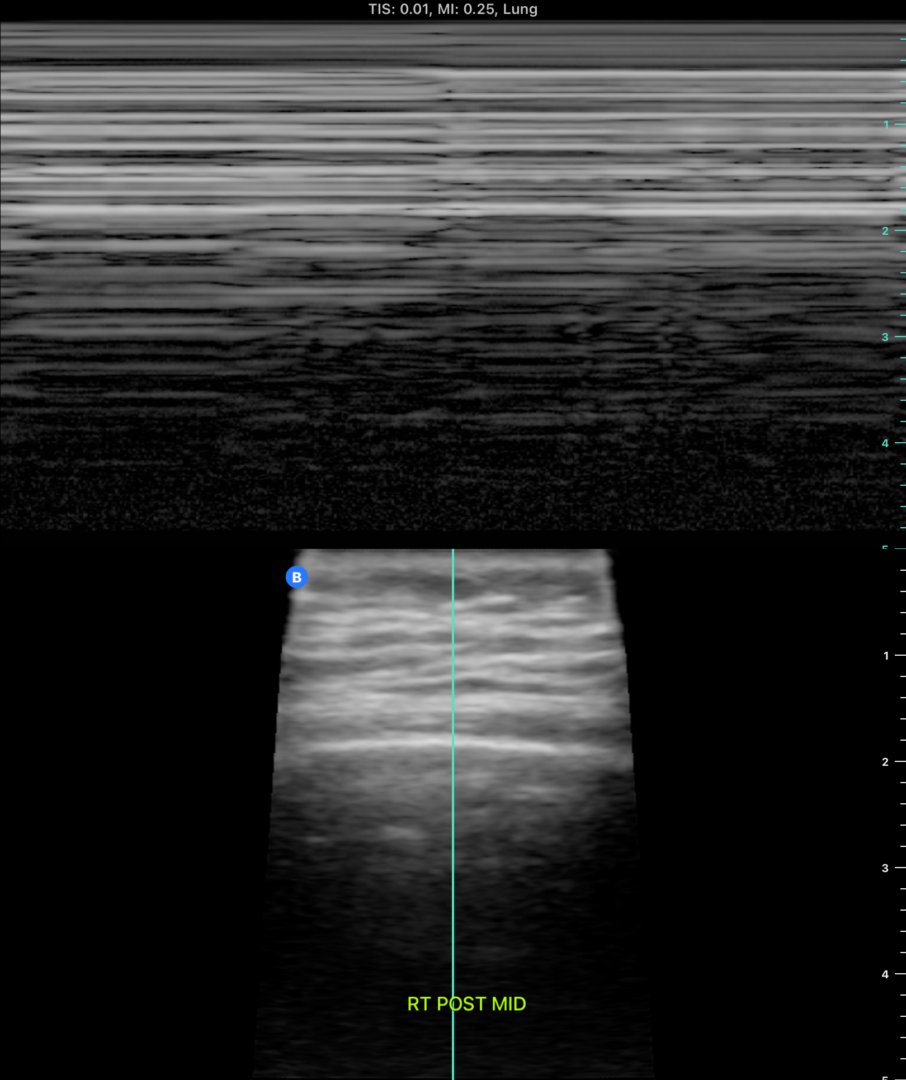

Pre-thoracentesis #POCUS of left posterior inferior view. Thoracentesis performed without complication, 1.5L removed and pt remained asymptomatic.

2/

3/